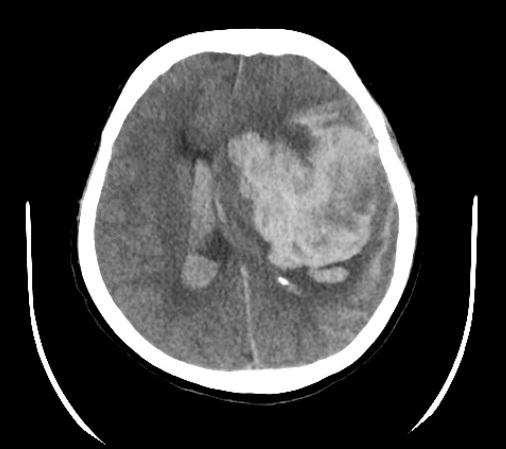

Case report: Hi guys, we had a patient come in with a massive head bleed. Intubated prior to CT. Neurosurgery came by to assess the patient after 40 min of (RSI) intubation. MD wanted to reverse Rocuronium with Sugammadex to do a full neurologic assessment for possible neurosurgical intervention.